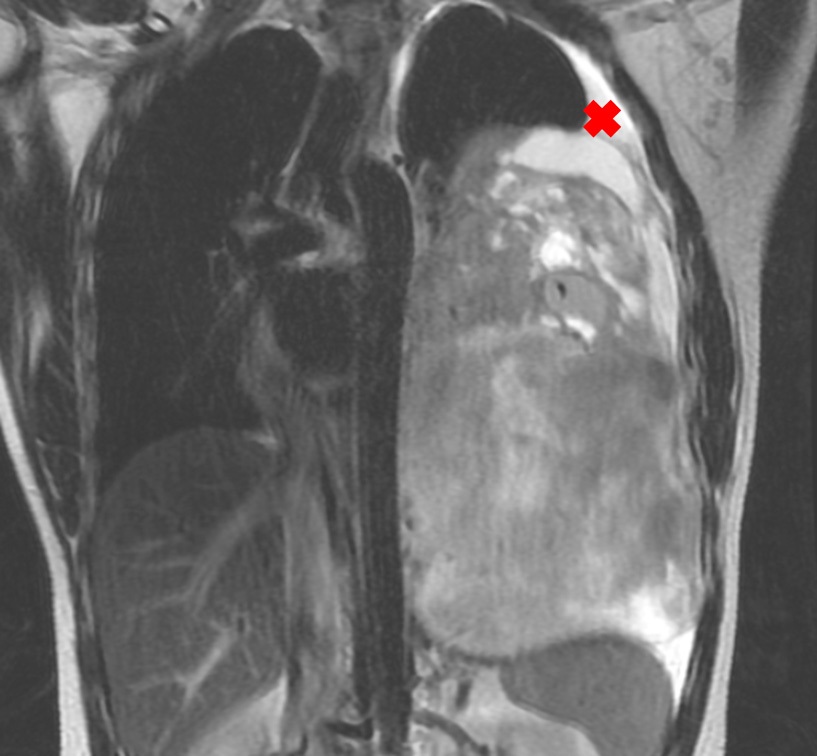

After the surgery, evaluation images in February, 2021 showed residual mass close to the descending aorta, the distal esophagus and the pericardial leaflet (Figure 2).

Right after the chemotherapy, he also received Stereotactic Body Radiation Therapy (SBRT) - 35 Grays in 5 sessions in June, 2021), as well as, to decrease the likelihood of disease increment. In vain, so the persistence of disease in contact with the pericardium, as showed in Figure 3, would progress shortly